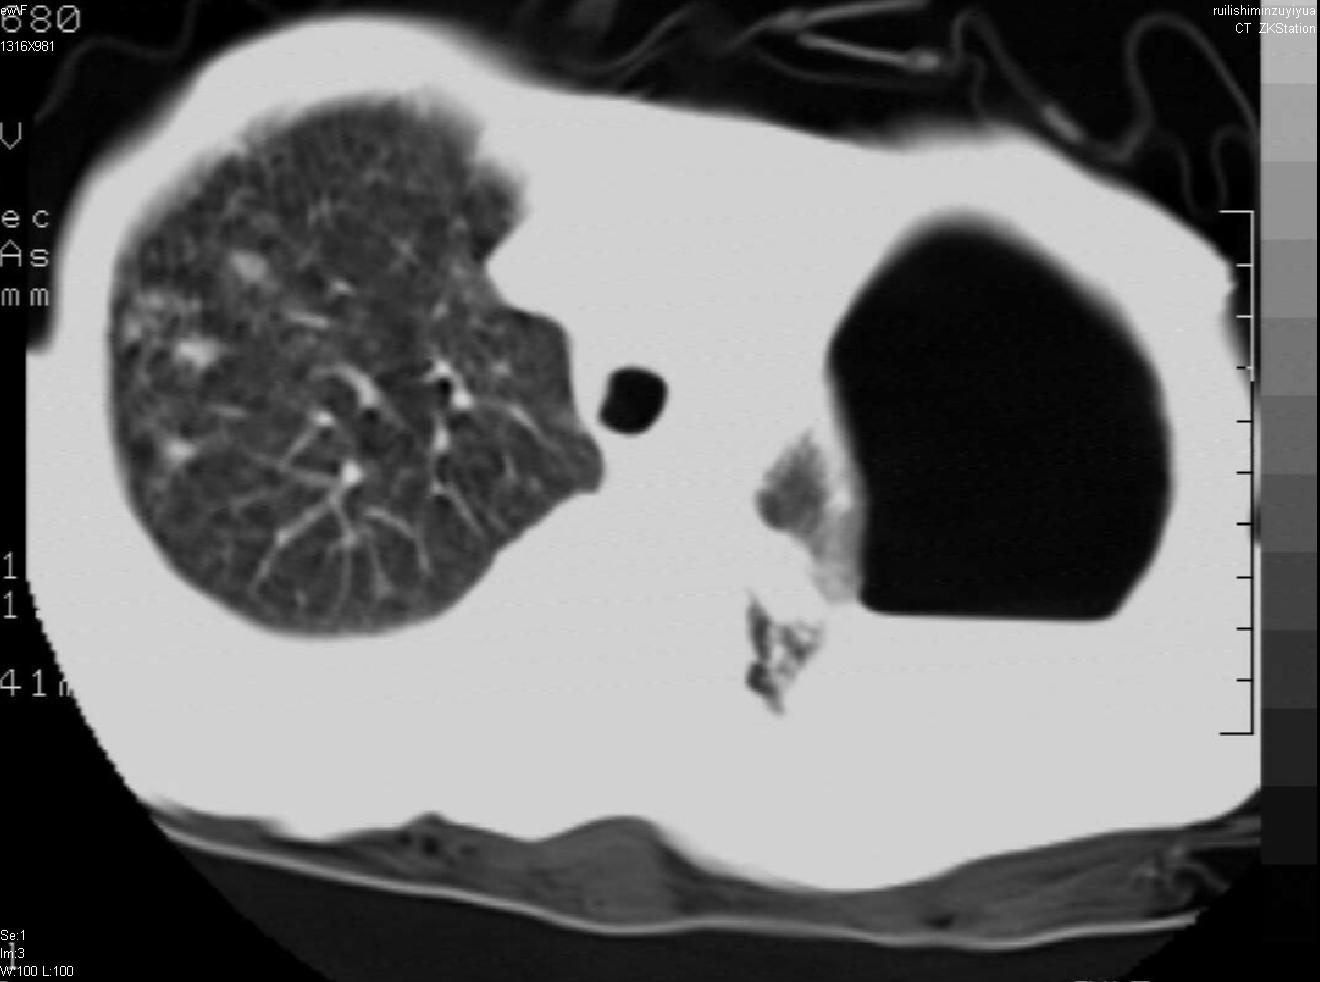

以下是引用天南地北在2007-6-11 23:32:00的发言:[br]1:左侧肺毁损(结核性)伴感染(多发空洞伴液平面)。[br]2:右肺继发型肺结核。

以下是引用avril在2007-6-12 1:17:00的发言:[br]1、左肺毁损。[br]2、左肺多发肺大泡伴自发性气液胸形成。[br]3、右肺继发型结核。

以下是引用尚峰在2007-6-11 22:44:00的发言:[br]慢阻肺、肺纤维化、肺大泡、气胸形成,此患者有没有急性病史?